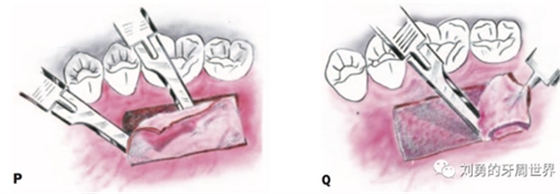

2、然后用15號刀片半厚瓣的方式取瓣,如下圖:

比如strip技術,如下圖:

上圖中,種植體唇側缺乏附著齦,從上腭取瓣,常規(guī)做法:取長而寬的齦瓣,這樣供區(qū)面積大,術后疼痛重。

為了減少痛感,從雙側上腭取多條長而窄的齦瓣進行移植,這樣每個供區(qū)的傷口都比較窄,可以減少術后的痛感。